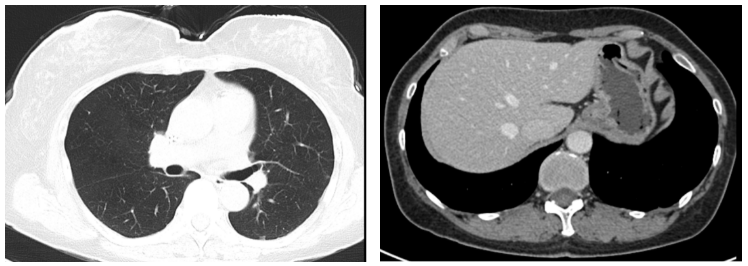

②二线治疗:紫杉醇380mg Q3W+原研曲妥珠单抗300mg Q3W+吡咯替尼320mg QD+唑来膦酸4mg Q4W;

两个疗程后复查CT:右乳Ca伴右腋下淋巴结M(较前相仿),伴两肺弥漫性转移(图3,较前缓解),肝脏转移灶消失(图3)。胸腰椎转移灶,较前相仿。疗效评价PR。

图3. 2019.03两肺转移灶(左图),肝左叶转移灶(右图)